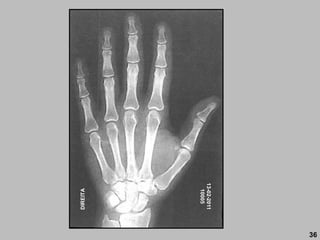

36

13-02-2011